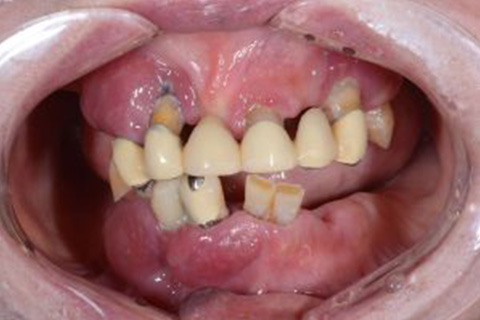

入れ歯の一番の悩みとして『見た目が悪い』。中でも前歯のワイヤーが嫌な方が多くおられます。トップの歯の写真を見てください。奥歯に少し金属が見られますが、唇で隠れるところなので、患者様は全く気にならずに、お友達とお食事や会話を楽しんでおられます。

症例1

歯がグラグラで噛めない。自然な入れ歯で綺麗にしたい。という主訴でご来院頂いた患者様に対して特殊プラスチックを使用した総入れ歯(入れ歯)とコーヌスクローネ義歯(入れ歯)の症例

術前

入れ歯での治療後